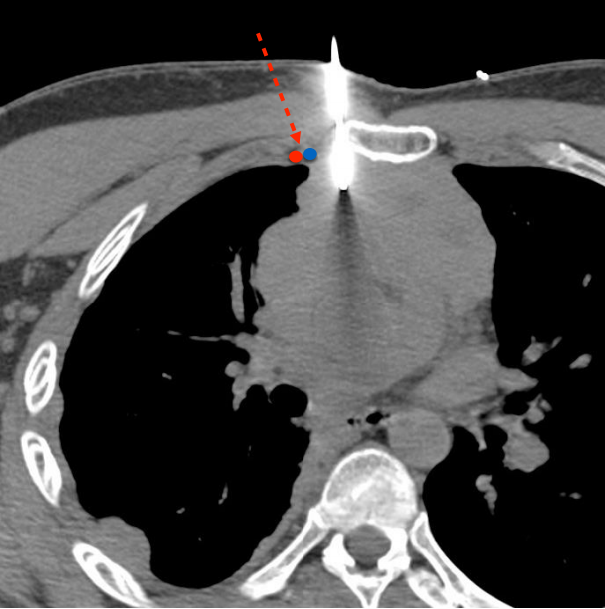

胸骨旁入路

Biopsy of Mediastinal masses parasternal approach

1. 注意两侧的乳内动脉